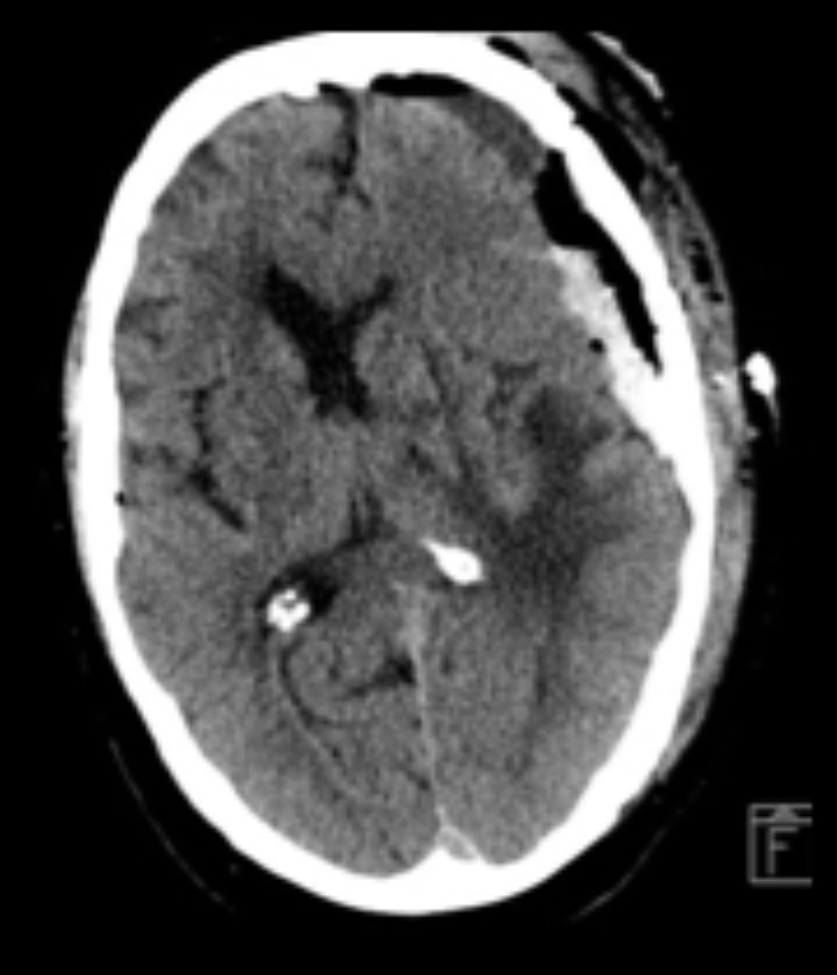

Sex differences in symptomatic intracranial hemorrhage and procedural complications after endovascular thrombectomy: Analysis of the OPTIMISE registry

Background

• There is heterogeneity in the literature with regards to differences in functional independence between men and women after endovascular thrombectomy (EVT) for stroke (1,2).

• Some studies suggest a lower likelihood of independence at 90 days among females, while others have found no difference when accounting for age, baseline functional independence, stroke severity and comorbidity burden (3).

• Differences in procedural complications and symptomatic intracerebral hemorrhage (sICH) between men and women after EVT is less well known.

•  This study aims to evaluate sex differences in sICH in patients who underwent EVT.

Methods

• OPTIMISE is a pan-Canadian prospective registry of patients treated with EVT across 20 sites and 7 provinces between 2018-01 and 2022-12.

• Using OPTIMISE data, we compared men and women with regards to baseline characteristics, functional outcomes and, as our primary outcomes, procedural complications and sICH

• sICH was defined  as a ≥4-point increase in the NIHSS score associated with the presence of parenchymal hematoma type 1 or 2 on follow-up CT, as determined by the treating physician

Results

3631 patients were included for analysis:

• Women were older (71.8±14.6 vs 68.0±13.1 years, p<0.001).

• There were no differences in median time from onset to puncture {232 (155-365) men vs. 235 (163-377) women, p=0.159}, and from puncture to reperfusion between sexes {(25 (17-37) vs. 24 (17-37), p=0.984}.

•  There were no differences in sICH rates {44 (2.5%) vs. 37 (2%), p=0.388}.

• Procedural complication rates were not different between men and women (5.8 vs 5.6% p=0.76)

Men

(N=1778)

Women

(N=1853)

p-value

Age (mean±SD)

68.0±13.1

71.8±14.6

0.001

Median (IQR) onset to puncture - min

232 (155-365)

235 (163-377)

0.159

Median (IQR) puncture to reperfusion - min

25 (17-37)

24 (17-37)

0.984

Tici 2b3

1446 (81.3%)

1554 (83.9%)

0.319

Tici 3

898 (50.5%)

1021 (55.1%)

0.264

sICH

44 (2.5%)

37 (2%)

0.388

Complications

• Dissection

• Perforation

• Embolization

• Arterial access

26 (1.5%)

11 (0.6%)

25 (1.4%)

45 (2.5%)

30 (1.6%)

7 (0.4%)

25 (1.3%)

43 (2.3%)

0.804

0.426

0.996

0.761

Table: Baseline characteristics in male and female

Bleeding complications in ischemic stroke3 e1619443612145

https://www.stroke-manual.com/hemorrhagic-complications-in-acute-stroke/

Conclusion

• There were similarly low and reassuring rates of sICH and procedural complications between men and women undergoing EVT in this large multicentre prospective cohort.

• Our findings complement previous studies that have demonstrated similar functional outcomes between men and women after EVT.